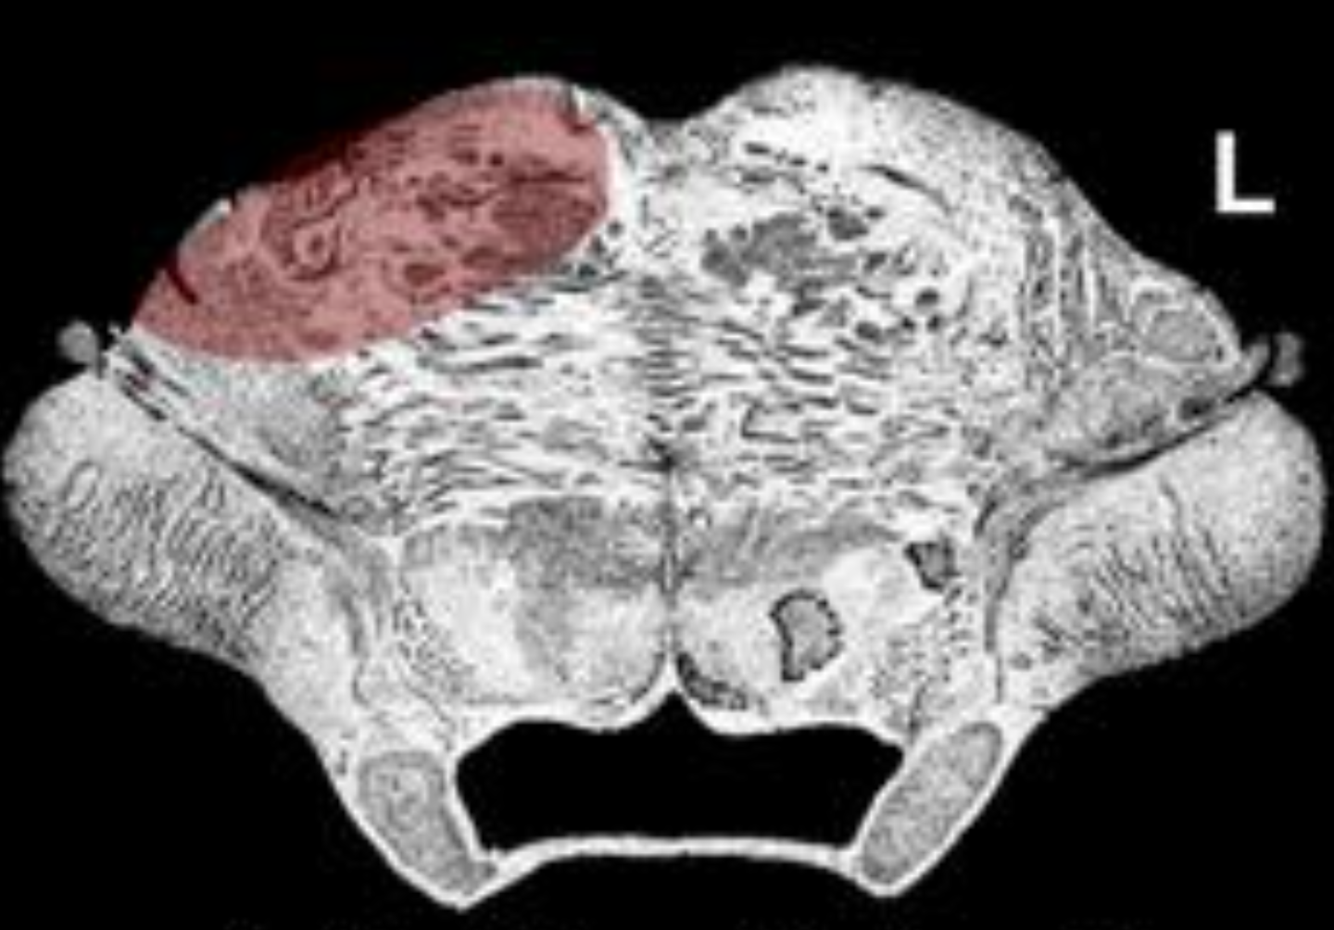

What is the name/location/results of the condition caused by a lesion in the shaded area?

pons and the level of the trigeminal n.

Alternating Trigeminal Hemiplegia with a Dorsal Expansion